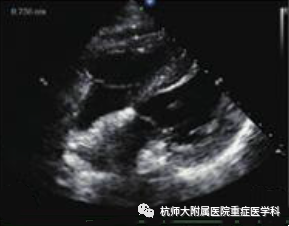

g.剑突下四腔心切面:位置选择:剑突下,超声探头声束朝向与房间隔平行,超声探头标记点指向左侧;操作中:(1)滑:超声探头从腹部向剑突下水平滑动;超声探头标记点指向受检者左侧;(2)倾:超声探头从水平方向缓慢向上倾斜,显露心脏;

什么是超声容积探头重症心脏超声图像的获取_https://www.jmylbn.com_新闻资讯_第25张什么是超声容积探头重症心脏超声图像的获取_https://www.jmylbn.com_新闻资讯_第26张

主要评估内容:(1)心包积液检查;(2)观察四个腔室及二尖瓣、三尖瓣的结构与运动;(3)评估右心室室壁厚度、房间隔缺损的最佳切面。